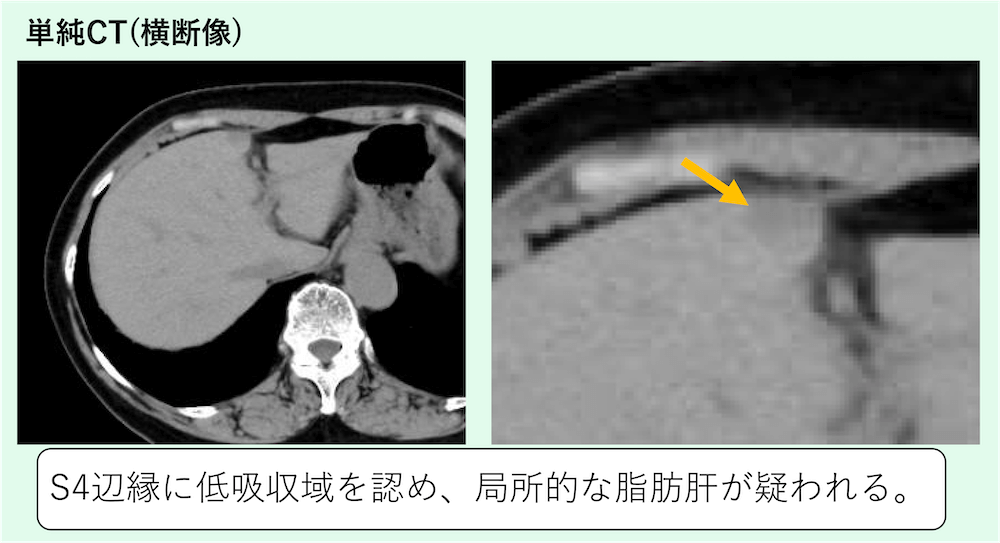

症例 60歳代女性

S4辺縁に低吸収域を認め、限局性脂肪肝(focal fatty liver)が疑われます。